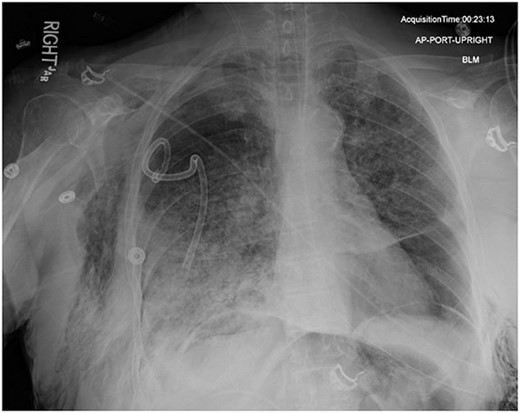

On Hospital Day 2, an interval CXR showed continued resolution of the right-sided pneumothorax but worsening subcutaneous emphysema of the bilateral chest wall and pneumoperitoneum (Fig. 3). Surgical consultation was sought, leading to diagnostic laparoscopy. In the abdomen, emphysematous changes within the gastrohepatic ligament and omental adhesions to the anterior abdominal wall were visualized (Figs 5 and 6). Laparoscopic exploration revealed no diaphragmatic injury or perforated viscera but identified emphysematous changes throughout the preperitoneal space, small and large bowel mesentery, and right paracolic gutter (Figs 7 and 8). Immediate post-op CXR no longer showed evidence of pneumoperitoneum (Fig. 4). The patient was transferred back to the ICU and extubated after three days on Day 5. After the removal of chest tube and transfer to a medical floor on Day 8, the patient developed aspiration pneumonia that was treated with antibiotics. She was discharged on Day 15.

Post-operative chest radiograph showing increased diffuse subcutaneous emphysema in chest, lower neck and upper left abdominal wall. Previously demonstrated pneumoperitoneum is not visualized on the current film.